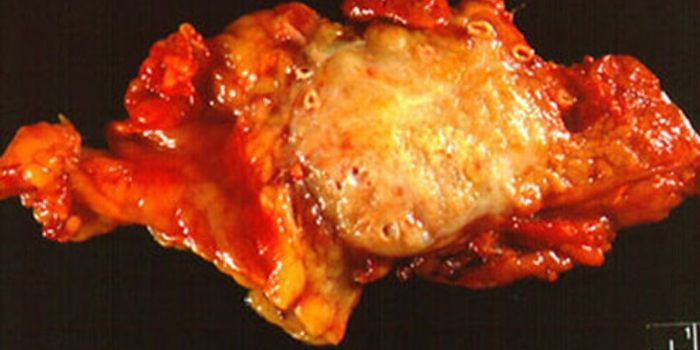

SEP 28, 2016ImmunologyA diet high in fat from specific sources is uniquely responsible for contributing to intestinal cancer through promoting ...